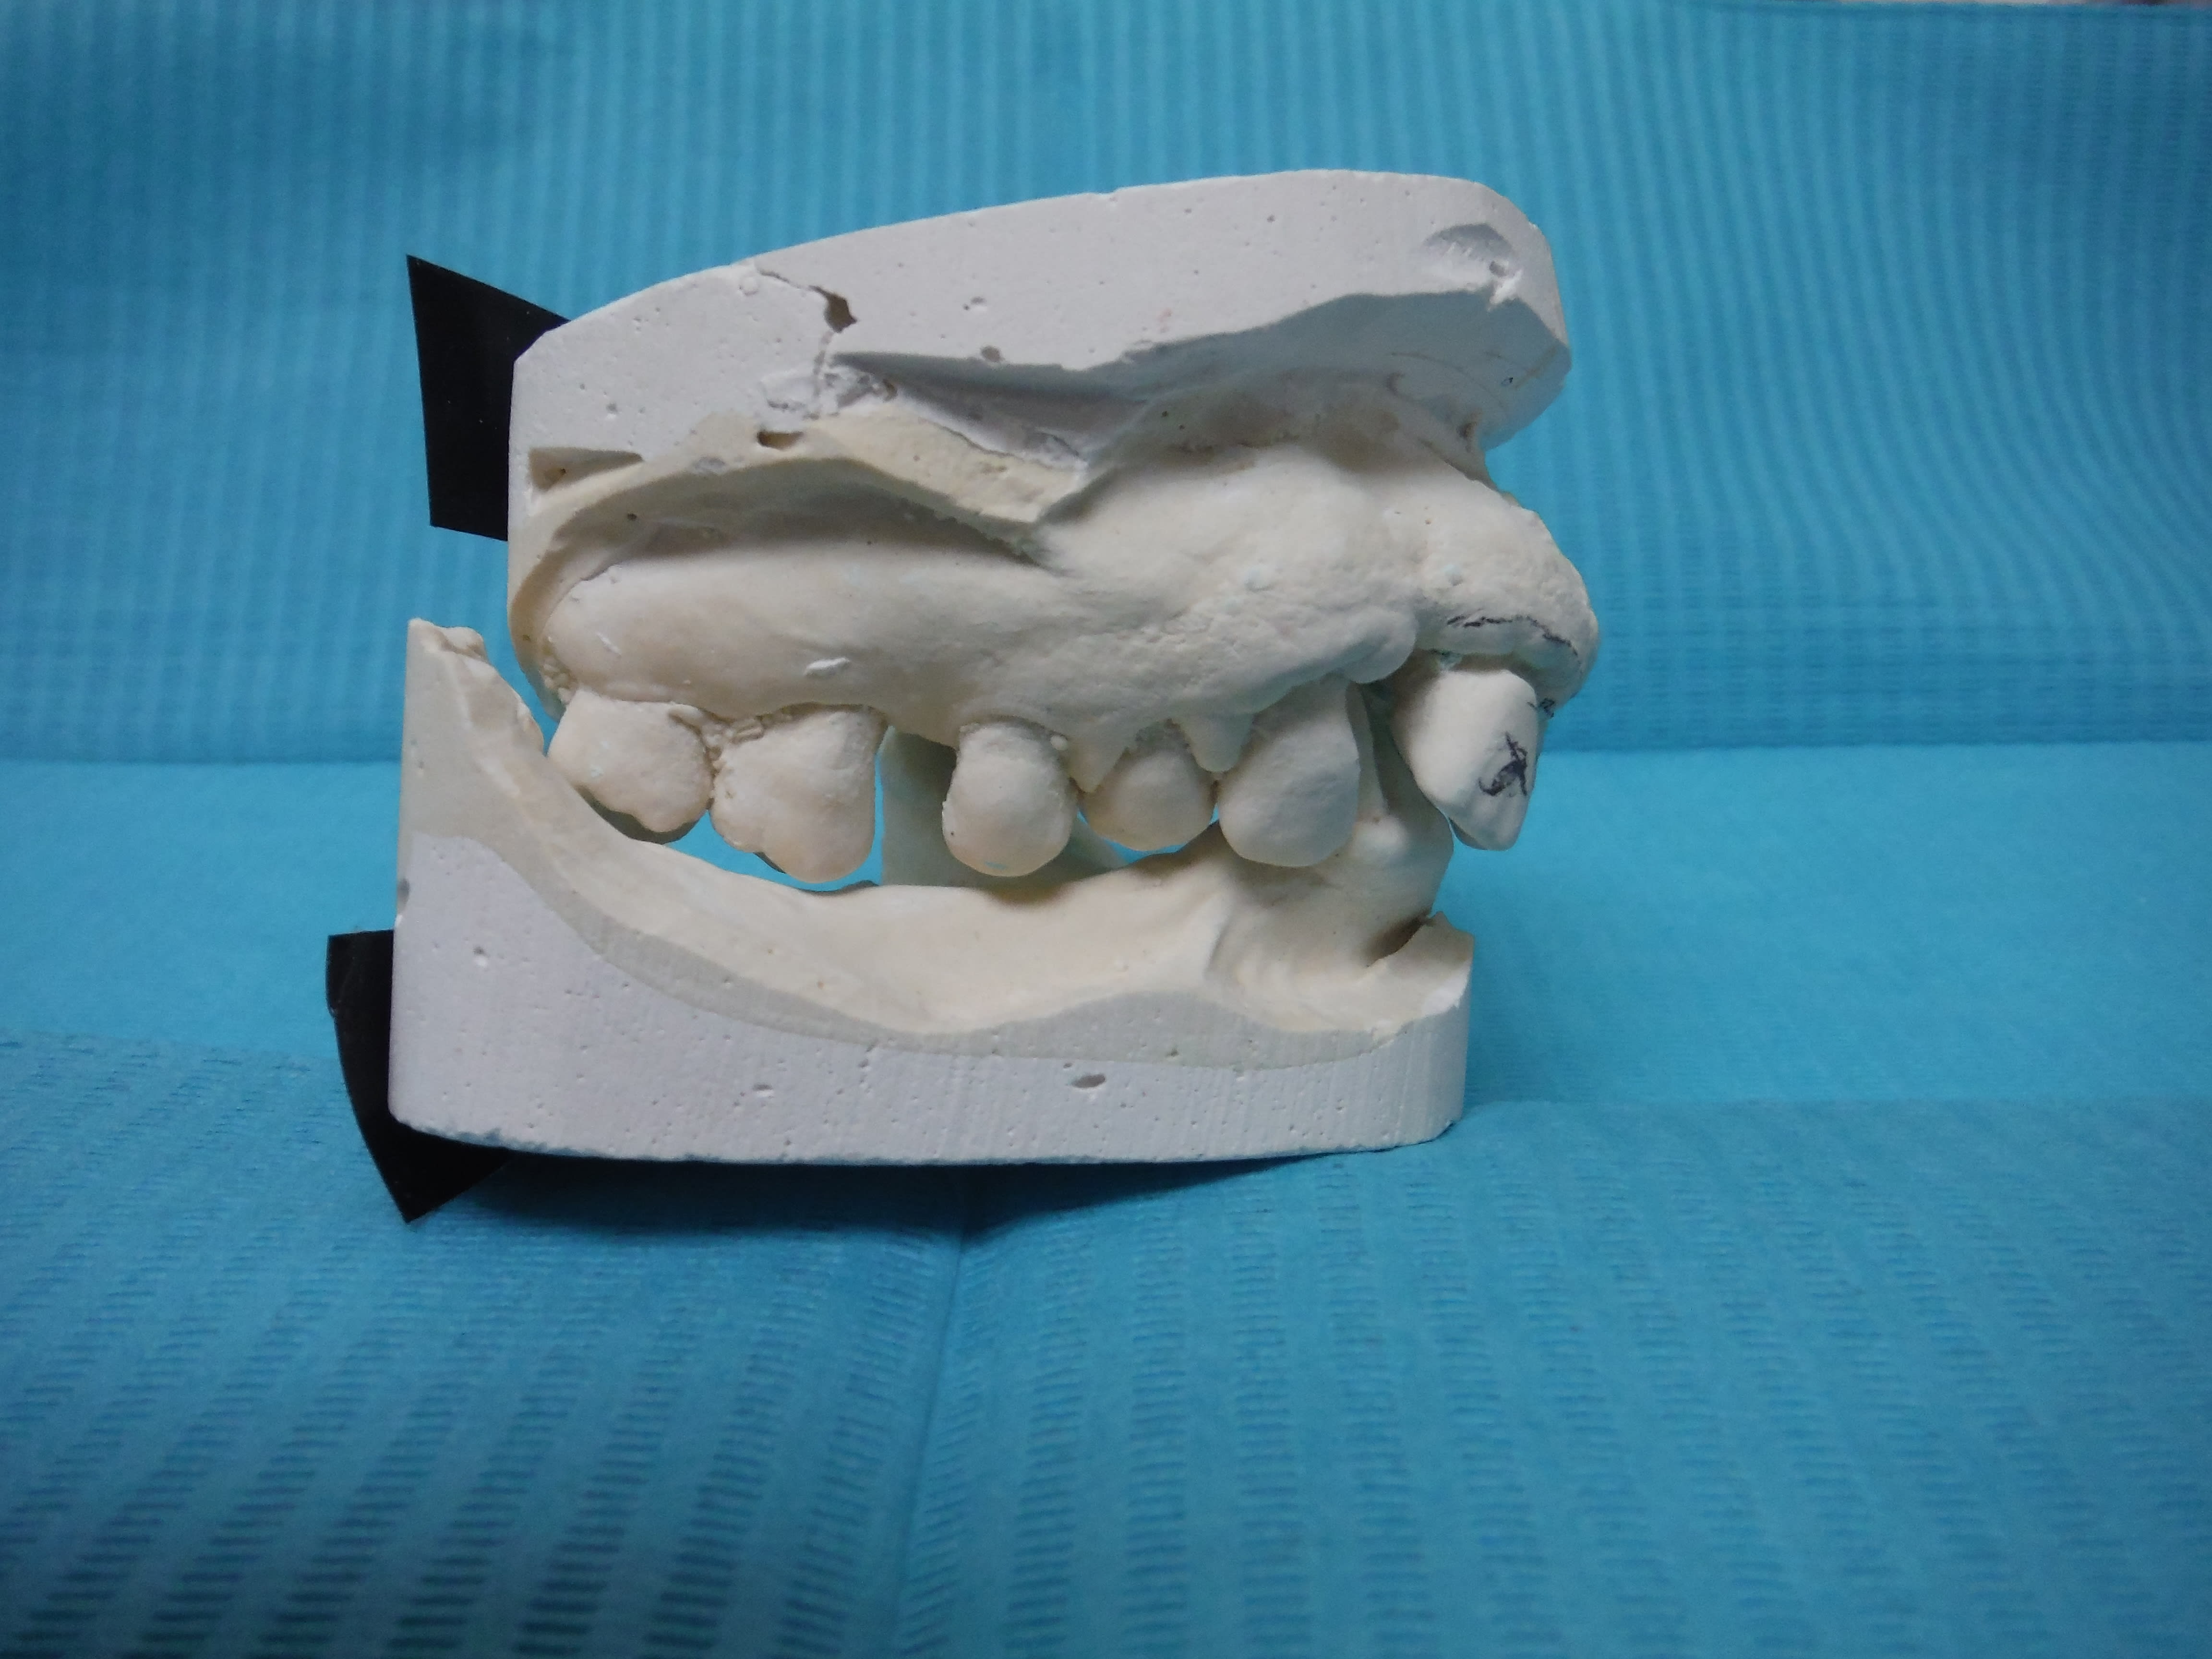

regardes ,l'empreinte etait propre ,et ben niqué CRAAC .

18 ans aprés peut etre ,mais niqué quand meme .

PS :le pion du milieu n'est pas un moyen de retention .

voilà ce qu'il menvoie la semaine passée.( il me l'a refait sur le meme platre )

comment veux tu que je lui fasse confiance pour IC+couronne ?.

en plus il m'a pienoirdisé l'empreinte .

- ç est quoi cte merde ?

* 1 IC ! tes collegues ,ils veulent tous ça et apres ils retaillent jusqu'au metal .